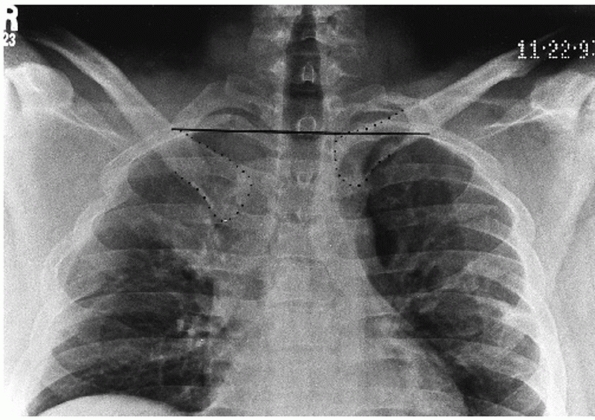

![]() |

FIGURE 40-5 A.

A 34-year-old patient was involved in a motorcycle accident and sustained an anterior blow to the chest. Note the symmetric anterior chest wall ecchymosis. B. CT reveals a left medial clavicle fracture without disruption of the SC joint. |

posteroanterior radiographs of the chest or SC joint suggest something

dislocation, radiographs and preferably a CT scan must be obtained to

confirm one’s suspicions (Fig. 40-5).